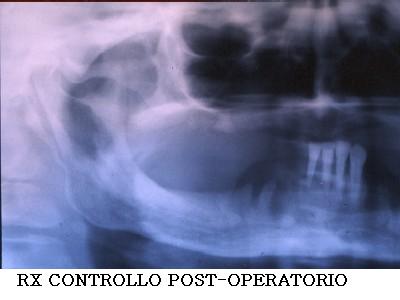

VOLUMINOSA CHERATOCISTI -

CISTI DEI MASCELLARI - ECTOPIC THIRD MOLAR